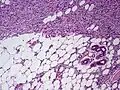

| Histopathological image of dermatofibrosarcoma protuberans. Local recurrence long after the first excision. H&E stain | |

Subcutaneous tissue infiltration (i.e. "honeycomb" growth pattern)